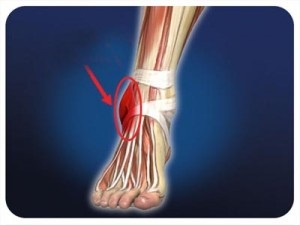

Glezna comun conecteaza oasele gambei cu piciorul, că acesta reprezintă cea mai mare sarcină atunci când mersul pe jos sau alergatul. Ligamentele dețin oasele articulației într-o anumită poziție.

Atunci când sarcină excesivă poate fi rănit ligamentare - grub sau complet rupt. În cazul deplasării accidentale neglijent de multe ori opri Tuck interior, care provoacă tensiuni. Acest lucru este facilitat de pantofi supraponderali, incomode (tocuri prea înalte), sport intensiv.

Simptomele unei tulpini glezna

ligament Torn poate fi vindecat doar o intervenție chirurgicală, dar dacă prejudiciul nu este puternic, este aplicat un tratament conservator. În plus față de utilizarea terapiei convenționale, vă puteți ajuta la remedii populare la domiciliu după consultarea unui medic.